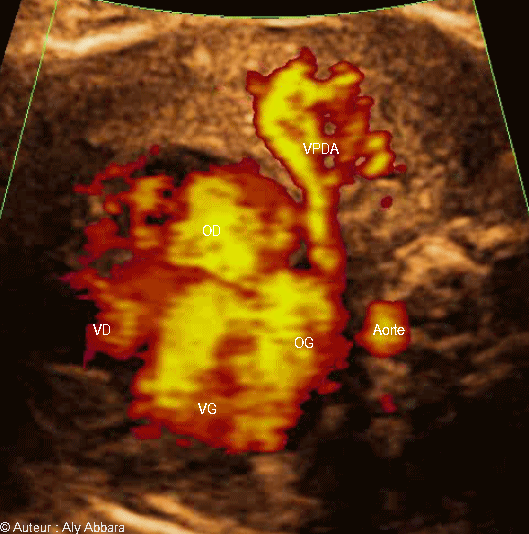

veine pulmonaire droite antérieure Veine pulmonaire droite postérieure

Images échographiques (avec la fonction Doppler-Energie) montrant les quatre veines pulmonaires ; ce sont les vaisseaux du retour veineux pulmonaire (des deux poumons) vers l'oreillette gauche.

Foetus âgé de 32 SA